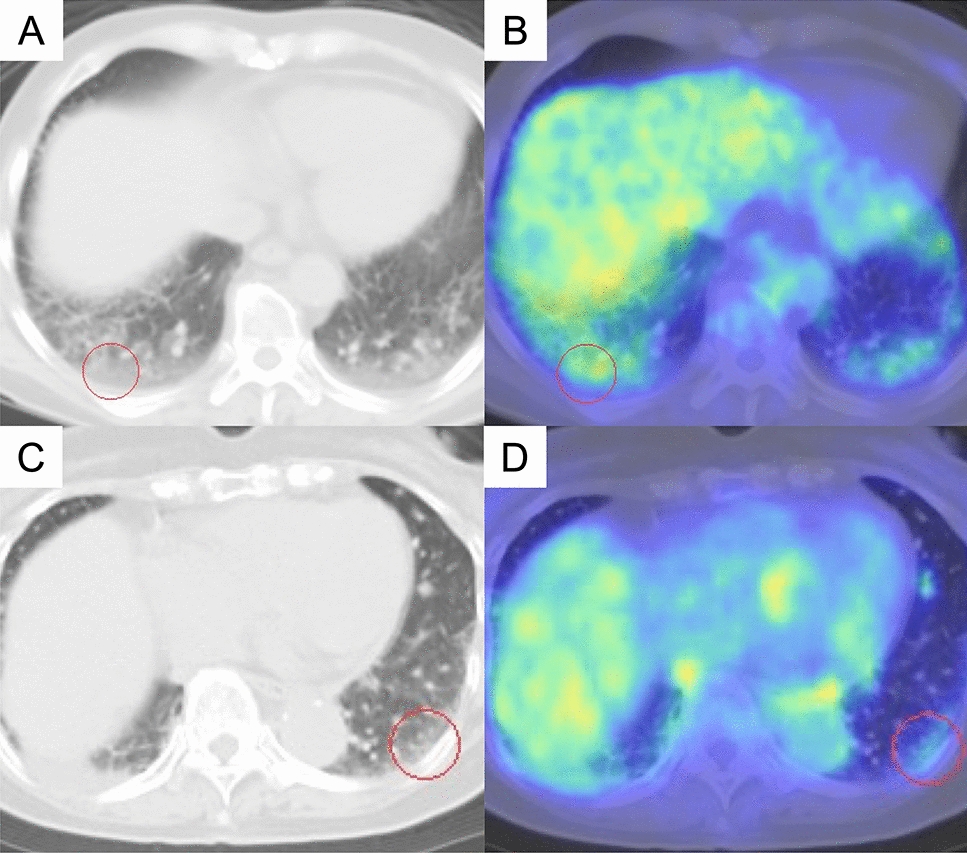

Association between FDG accumulation in interstitial lesions and acute exacerbation risk in lung cancer: multicenter analysis

Interstitial pneumonia (IP) is associated with poor prognosis in lung cancer and increases the risk of acute exacerbation ...